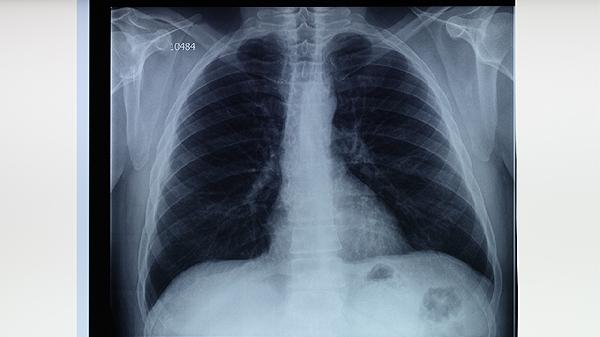

肺结核患者日常饮食需保证每日2500毫升饮水,优先选择清蒸鱼、蛤蜊豆腐汤等低盐做法。治疗期间每周摄入20种以上食物,适当增加乳制品和绿叶蔬菜。保持规律作息与适度运动,每月监测体重变化,出现咯血或持续低热需及时复查胸片。康复期可进行八段锦等柔缓运动增强肺功能,避免进食辛辣刺激食物影响药物疗效。